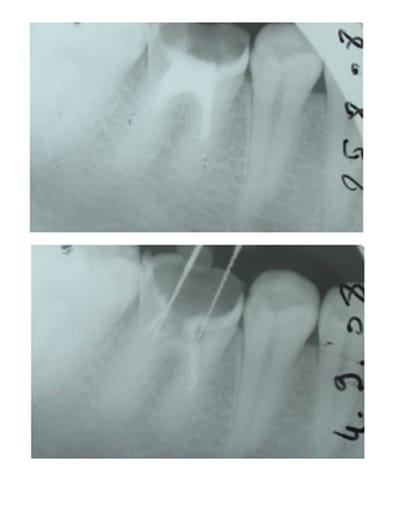

Je viens d'en récupérer une sur une 36 chez un nouveau patient de 30 ans, pan lingual cassé cet été, canaux totalement calcifiés, j'arrive pas à passer, aucune lumière (je sais je n'en suis pas une non plus hélas...). Que faire?

sur la 36 du trentenaire,j'arrêterais tout avant les faux canaux:de plus il ne semble pas y avoir de pb apicaux?

2-La 36 du trentenaire va très bien au niveau apical. J'ai besoin des canaux pour la reconstituer, je vais donc me contenter d'enlever le ciment à base d'eugénate... au risque de me voir reprocher de ne pas avoir boucher les racines "correctement". Je trouvais juste bizarre qu'il n'y ait plus de canaux, au delà de ce que j'ai appelé une pulpo ancienne (basse j'en conviens).